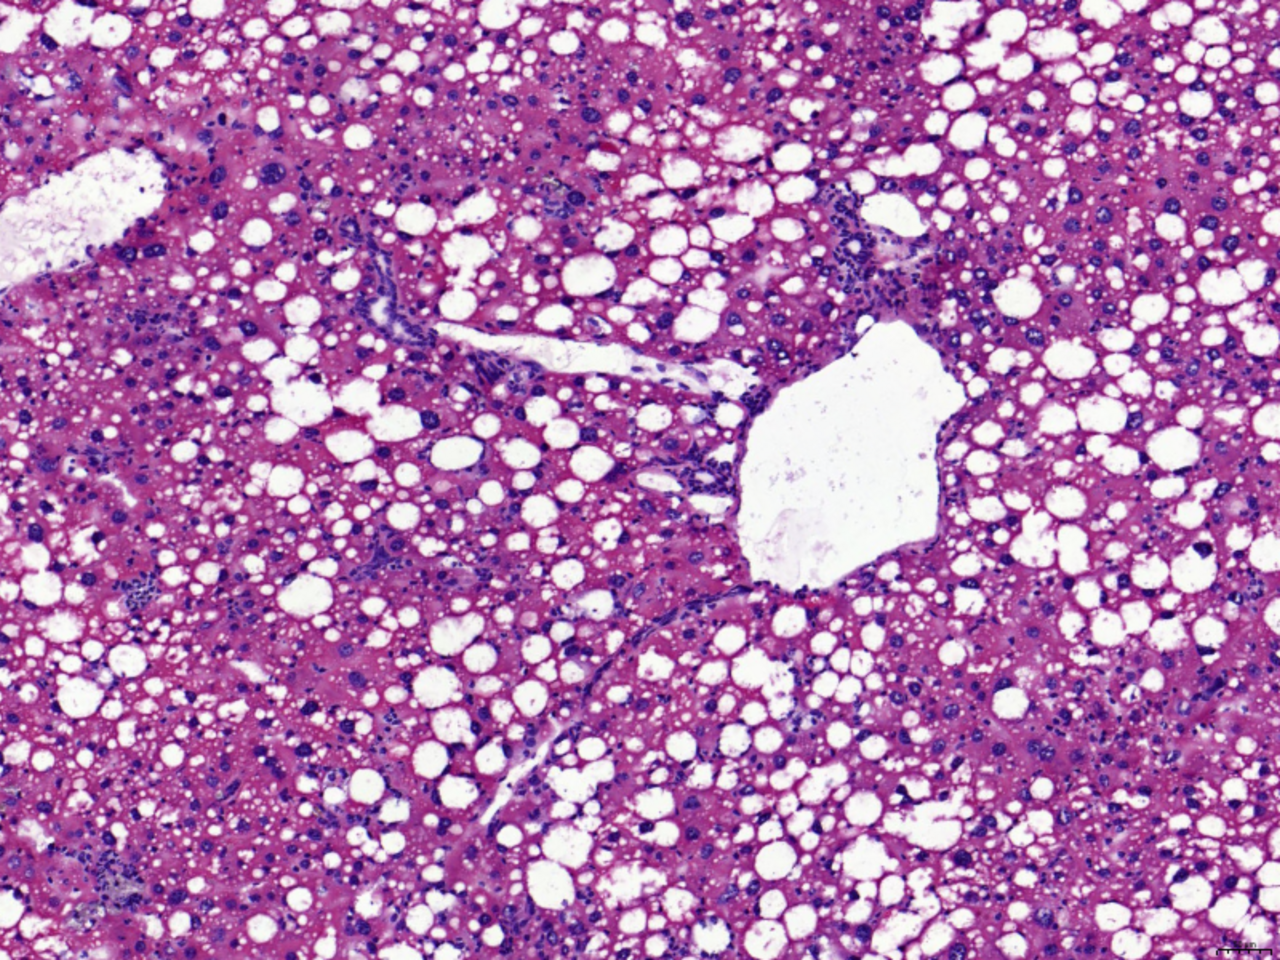

One of the primary aspects of the study is the evaluation of the selected MASH mouse model induced by a combination of a high-fat diet (western diet) and carbon tetrachloride (CCl4). This model closely resembles human MASH pathology and metabolic alterations, particularly in lipid metabolism and energy production pathways. Through TDMPA, we demonstrated the model's resemblance to human MASH, thus validating its suitability for studying the disease's pathophysiology and developing treatment strategies. We observed that the most affected parts of the liver metabolism were bile acid biosynthesis and recycling, fatty acid beta oxidation, biosynthesis, and metabolism, cholesterol biosynthesis, metabolism, and esterification, leukotriene and arachidonic acid metabolism, carnitine shuttle, oxidative phosphorylation, phospholipid biosynthesis, sphingolipid biosynthesis, and the metabolism of multiple amino acids.